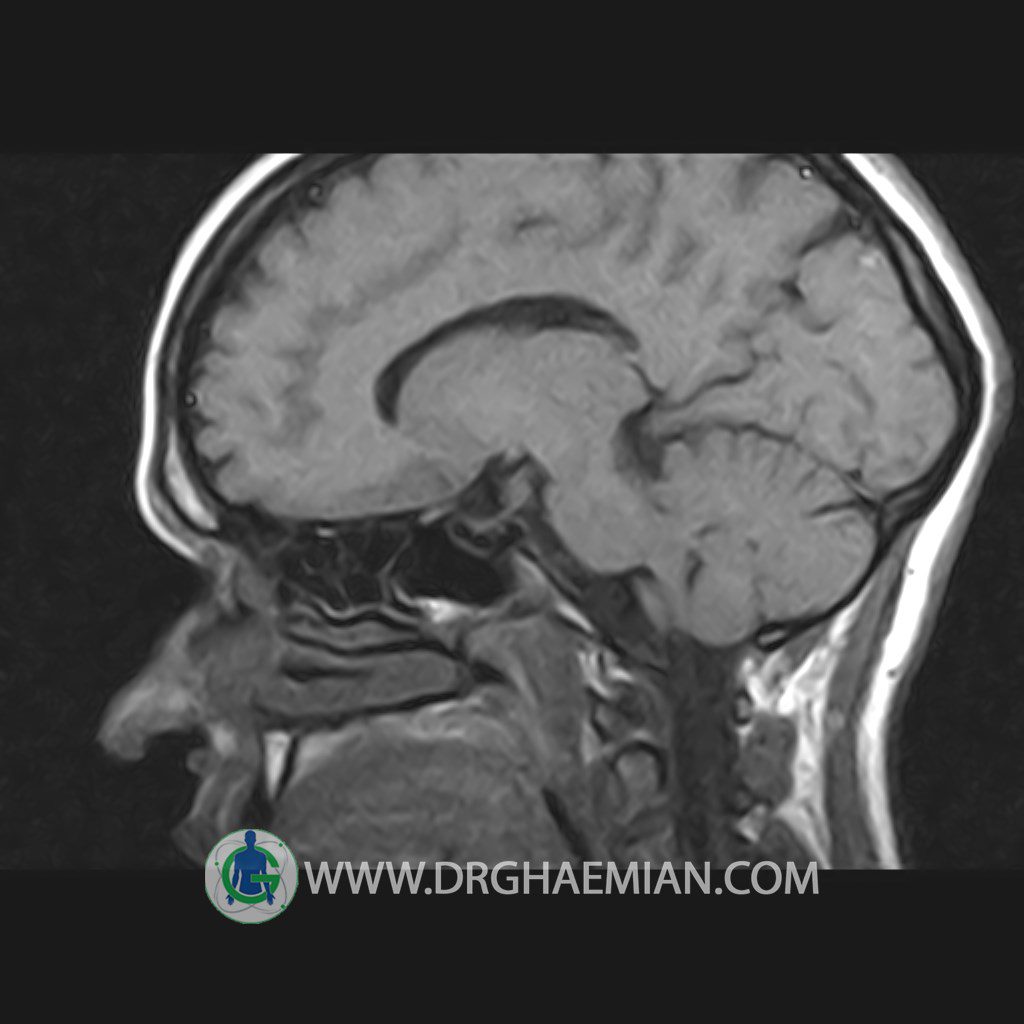

پزشکان اغلب از تصویربرداری ام آر آی برای تشخیص و درمان عارضه های پزشکی که فقط با استفاده از اشعه ایکس یا میدان مغناطیسی و امواج رادیویی قابل مشاهده است، استفاده می کنند. دستگاه ام آر آی تصاویر دقیق از ساختار های داخلی بدن ایجاد می کند. در این کیس هیپرپلازی هیپوفیز و آدنوم مشاهده می شود.

HYPOPHYSIS MRI

(with and without contrast)

Technique: Axial , coronal T1 , Axial , coronal , sagittal T2 , Axial, coronal T1 post Gd & 64 dynamic thin coronal slices.

REPORT :

The sella shows normal size , position and configuration .

The borders of its floor and walls are smooth and sharply defined .

The infundibulum is centered and of normal size .

The optic chiasm and suprasellar spaces appear normal .

The cavernous sinus and imaged portions of the internal carotid artery and carotid siphon are unremarkable .

Evaluable portions of the neurocranium show no abnormalities .

The sphenoid sinus is clear and pneumatized .

– Mild convexity at superior border of pituitary gland with post contrast homogeneous enhancement suggestive for pituitary hyperplasia & iso signal adenoma

is seen